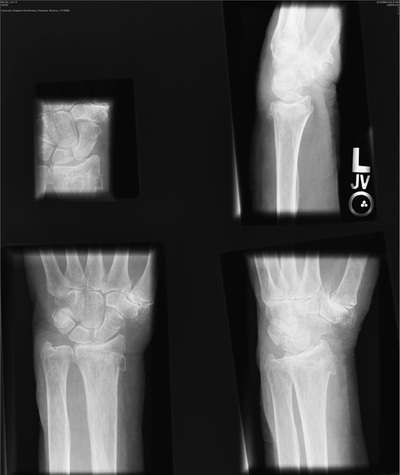

If the x-ray exposure field is not properly collimated, sized, and positioned, exposure field recognition errors may occur. These can lead to histogram analysis errors because signal outside the exposure field is included in the histogram. The result is very dark or very light or very noisy images (Figure 21-15).

Collimation of the projected area x-ray beam is important for patient radiation dose reduction and for improved image contrast in screen-film radiography. In DR, proper collimation has the added value of defining the image histogram. If improperly collimated, the histogram can be improperly analyzed, resulting in an artifact such as that shown in Figure 21-16.

For the image histogram to be properly analyzed, each collimated field should consist of four distinct collimated margins, as seen in Figure 21-18. The use of three collimated margins usually works, but when fewer than three are used, artifacts may result.

Alignment of the exposure field on the IP is important in the same way and for the same reason as collimation. When an image field, such as that shown in Figure 21-20, is not oriented with the size and dimensions of the IP, image artifacts can appear.